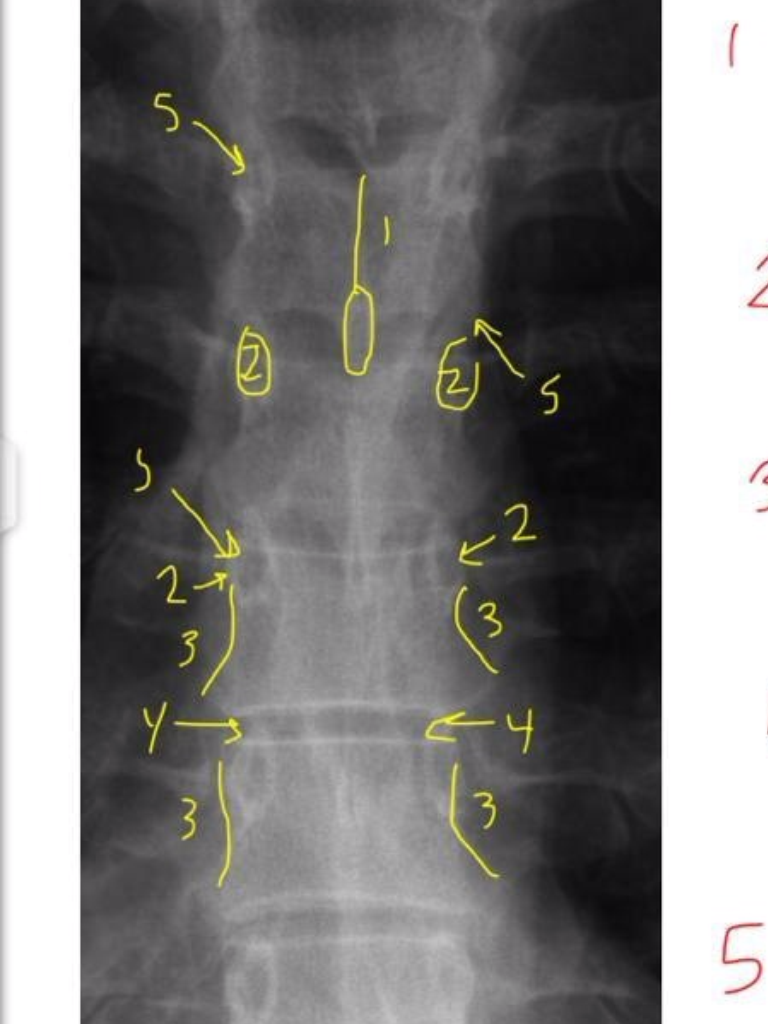

Junction of laminae

Pedicle Shadows

vertebral waist

Disc Spaces

Endplate Tips